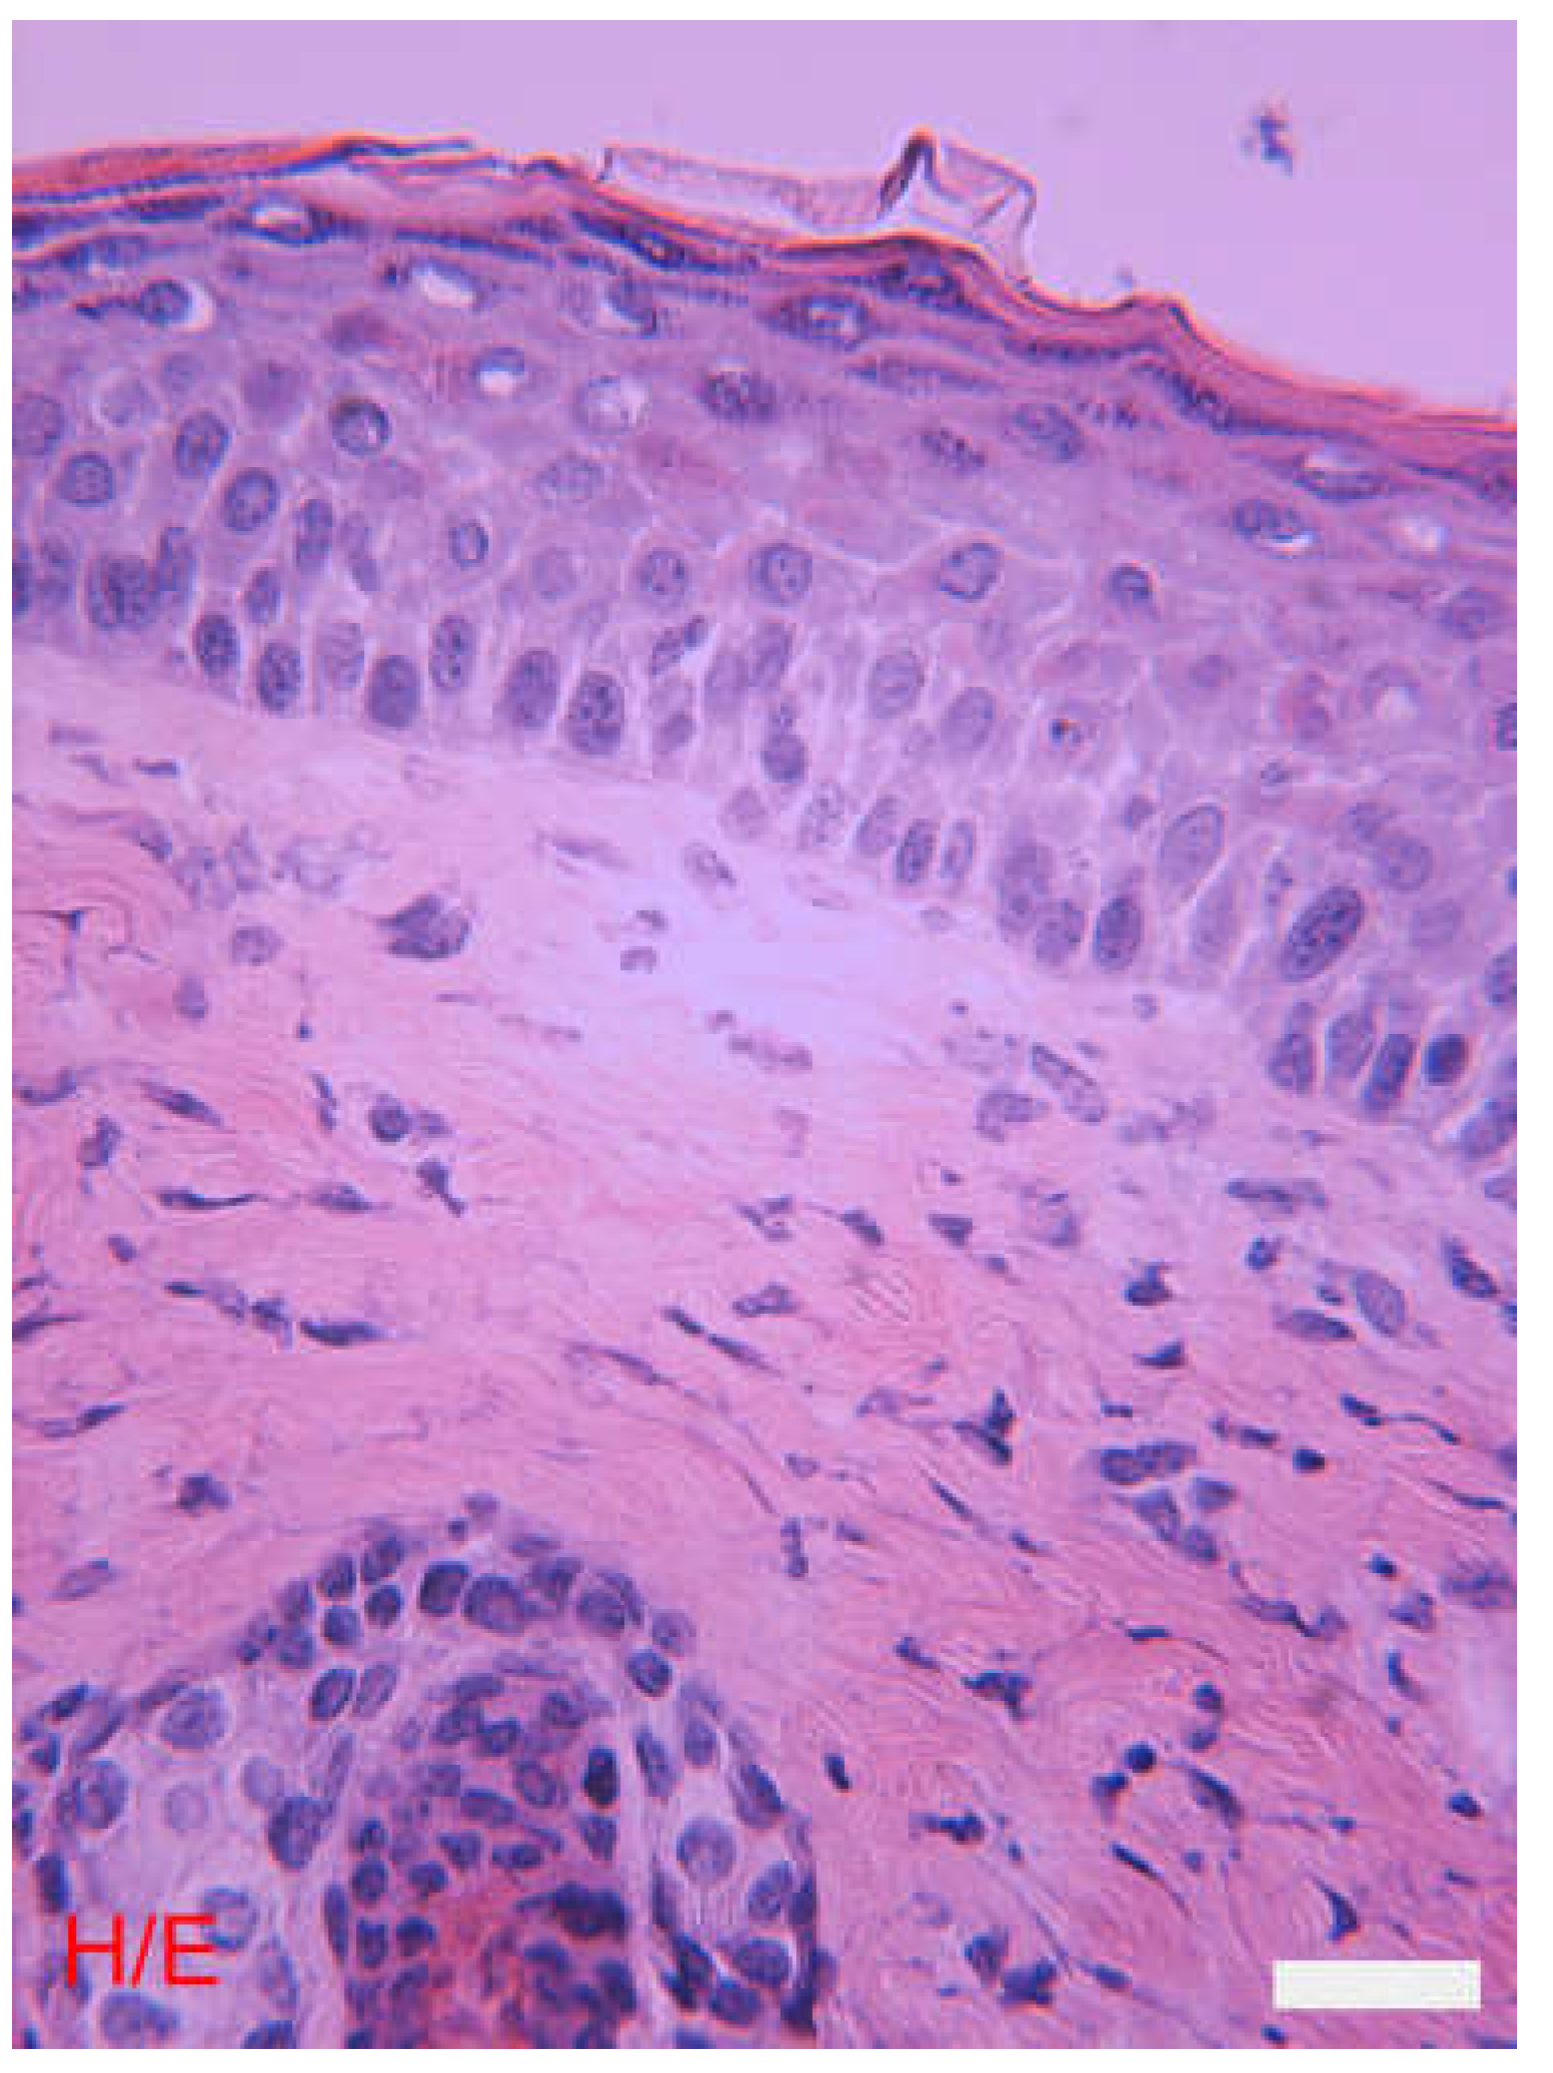

General Morphological Characteristics of the Skin

The Epidermis

The Dermis